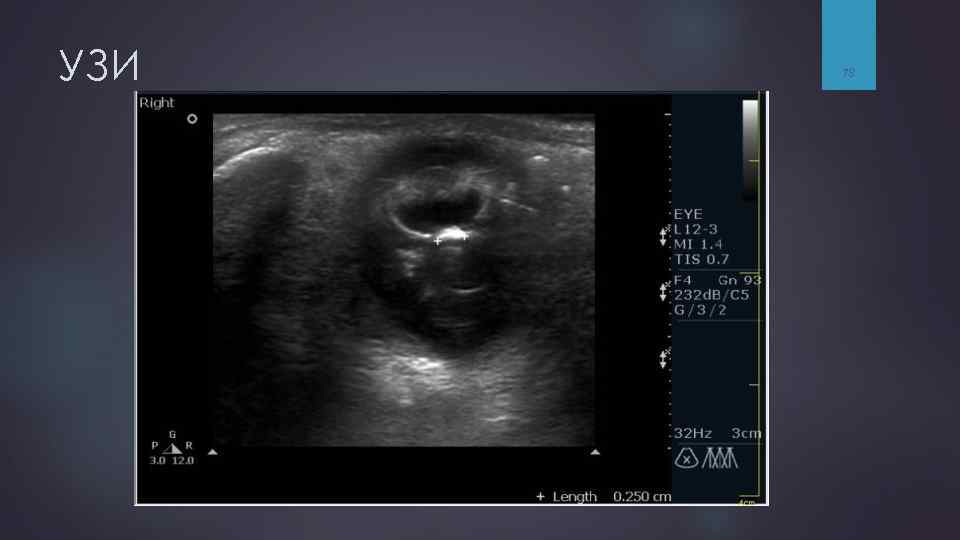

Ультразвуковое исследование (УЗИ) УЗИ применяется для диагностики: сочетанных повреждений лицевого скелета и структур орбиты, § §позволяет §а выявить гемофтальм, отслойку сетчатки, также оценить эти состояния в динамике. Ограничением метода является невозможность оптимально оценить состояние костных структур. 77

УЗИ 78

УЗИ 79